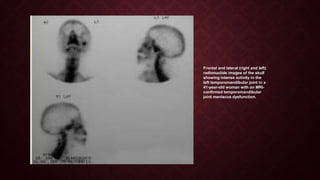

Frontal and lateral (right and left)

radionuclide images of the skull

showing intense activity in the

left temporomandibular joint in a

41-year-old woman with an MRI-

confirmed temporomandibular

joint meniscus dysfunction.

Frontal and lateral(right and left) radionuclide images of the skull showing intense activity in the left temporomandibular joint in a 41-year-old woman with an MRI- confirmed temporomandibular joint meniscus dysfunction.